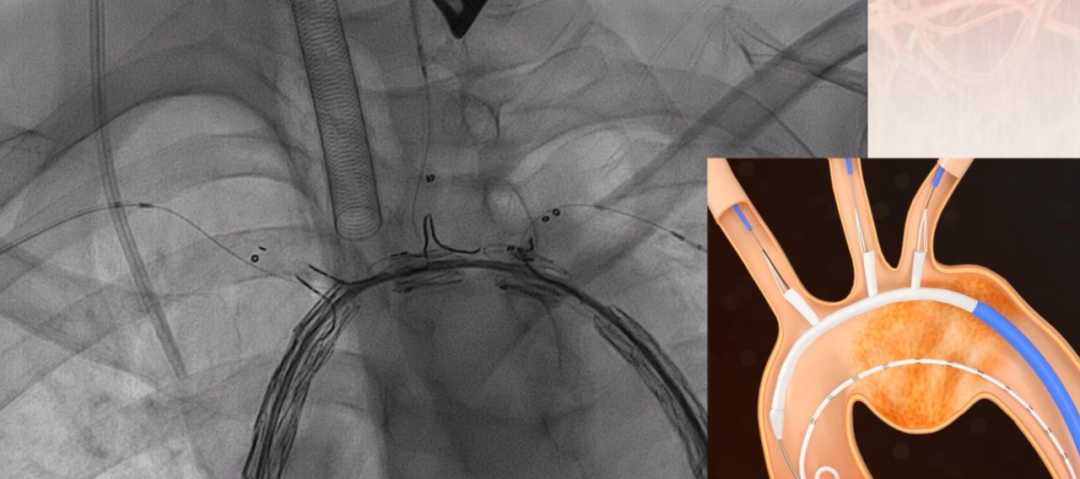

同时,考虑到患者拒绝开胸手术,为在保证治疗效果的前提下最大程度降低手术创伤,医疗团队综合评估后,决定采用FixTa一体化三分支型主动脉覆膜支架行胸主动脉覆膜支架腔内隔绝术+无名动脉、左颈总动脉、左锁骨下动脉分支重建术。该方案旨在通过腔内介入技术,精准修复主动脉夹层,恢复主动脉正常血流,同时减少手术创伤及并发症风险。

一体化三分支型主动脉覆膜支架

根据详细测量数据,选用型号为 F46-40-45-191-16-14-14 FixTa一体化三分支主动脉覆膜支架支架系统。

调整支架位置,确保主体分支支架对应无名动脉、左颈总动脉及左锁骨下动脉开口位置满意。

本次一体化三分支主动脉覆膜支架腔内治疗陈旧性主动脉夹层手术的成功实施,展示了复杂主动脉夹层腔内治疗的前沿技术,为累及弓部主动脉病变治疗提供了重要的实践依据和参考经验。该支架突破传统腔内治疗对弓部分支解剖的限制,结合防缠绕导管的精巧设计和导丝牵引技术,使手术操作更加精准简便省时,同时避免了开胸手术的创伤,缩短术后恢复时间,为今后治疗类似复杂病例提供了一种治疗选择。